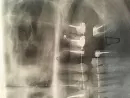

Три дня назад мне установили имплантаты. Один из них вместо четвёртого зуба слева на верхней челюсти. У меня постоянная ноющая боль только в этом месте. На снимке видно, что имплант установлен близко к соседнему здоровому зубу. Снимки до и после операции.

Может ли это быть причиной этой боли? Нужно ли его переустановить?

По ортопантомограмме определить точное положение импланта невозможно, необходимо сделать снимок КТ для определения точного взаимоположение зуба и имплантируемого элемента. Рекомендуем обратиться к хирургу-стоматологу, проводившему операцию.